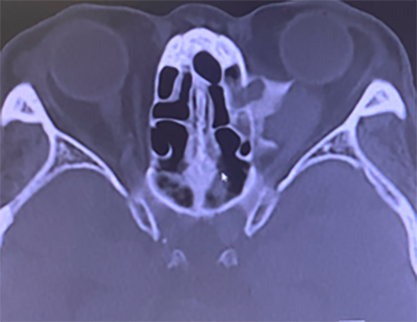

眼窩内合併症(CT)

CTにて眼窩内合併症が疑われる。